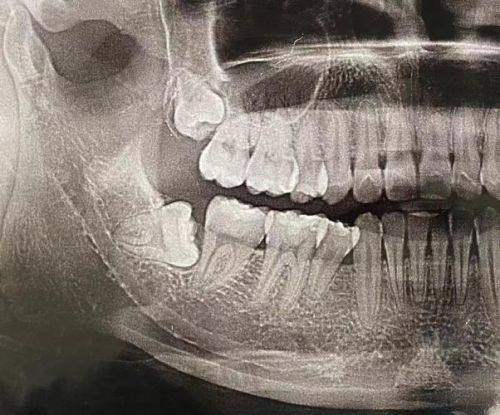

拔智齿的价格并非固定不变,而是受到多种因素的影响。首先是智齿的生长位置,如果智齿完全萌出,且生长方向正常,拔除相对简单,费用一般在几百元左右。但如果智齿是阻生齿,比如水平阻生、倒置阻生等,拔除难度大,需要切开牙龈、去除部分牙槽骨,费用就会大幅增加,可能在一千元到数千元不等。此外,医院的等级和地区差异也会对价格产生影响。在一线城市的三等甲医院,收费通常会比二三线城市的小诊所高。